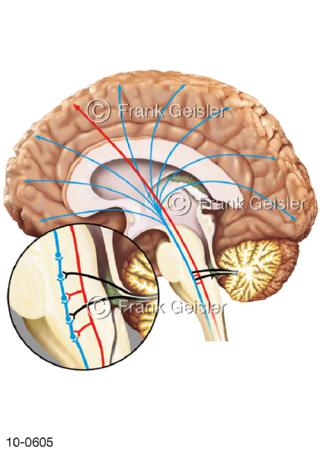

Bildergalerie Nervensystem

Bilder zum Nervensystem,dem Gehirn, Teil des zentralen Nervensystem, Zentralnervensystem ZNSmit Rückenmark, Abbildungen zum Nervengeflecht (Nervenplexus), die Verflechtungen von Nervenfasern, aus der Wirbelsäule hervortretende Nervenäst sowie Nervenzellen der Nerven